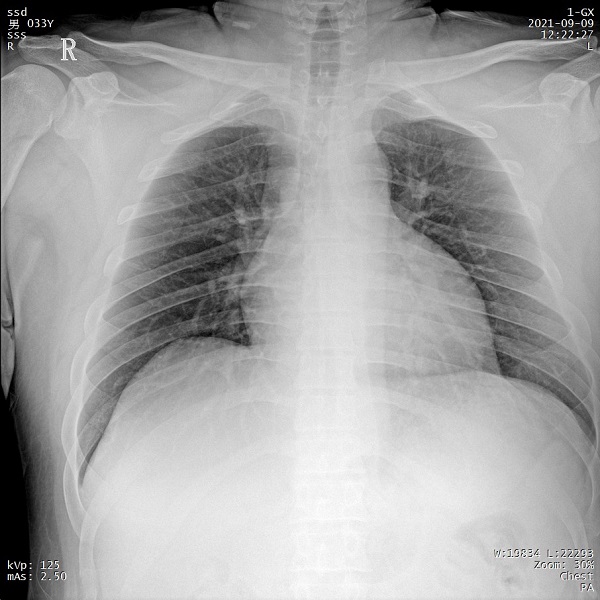

二、1ms 短時曝光 定格心肺運動瞬間影像

PLX5500系列移動DR能夠在1ms的曝光時間內(nèi)輸出足量的X射線,獲取清晰圖像。特別適用于拍攝肺炎、塵肺病、肺結(jié)核等難以憋氣的患者,避免了因患者肺部呼吸運動而產(chǎn)生的運動偽影的影響,瞬間定格清晰圖像,以供醫(yī)生準(zhǔn)確診斷。

三、支持高千伏攝影 肺部紋理更有層次

PLX5500系列移動DR的可調(diào)千伏達(dá)到150kV,在達(dá)到一定高電壓后,與骨骼相重疊的軟組織或骨骼本身的細(xì)小結(jié)構(gòu)及含氣的管腔等,均可清晰顯示。